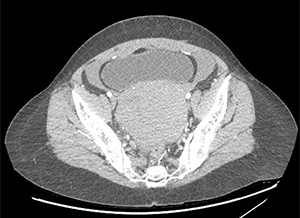

Case date: October 2018

This 39 year old female presented to the ED complaining of two days of lower abdominal pain and cramping. Her pregnancy test was negative.

Question 1 : What’s wrong with these pictures?

There is a large hemoperitoneum (arrow below) with a massive rectouterine structure (star below) concerning for clot.